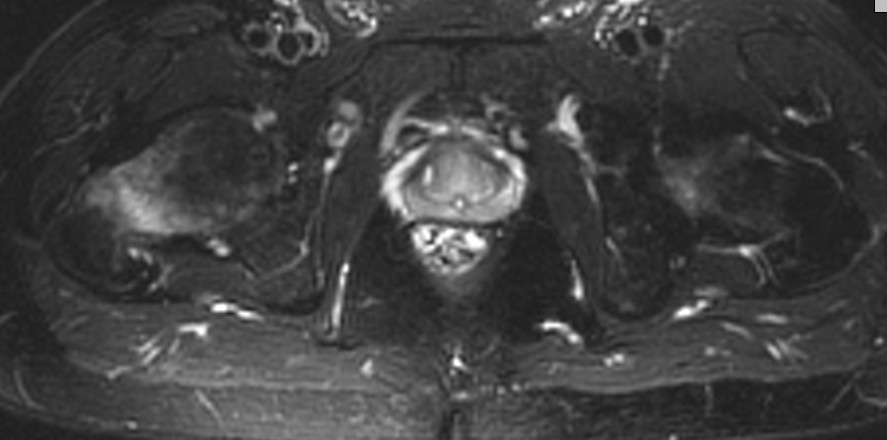

Двухсторонняя патология указывает на стрессовый перелом шейки. По характеру стрессовые переломы разделяются на тензионный в верхнем отделе у пожилых и компрессионнный в медиальной стороне у молодых.

Встречается обычно у бегунов или у активных молодых. МРТ более информативна, чем остальные исследования. Профилактическая перкутанная фиксация винтами поможет уйти от болезненного состояния.

Во вложении похожий случай. Пациентка 50 лет решила подготовиться к любительскому марафону и в течение 2 месяцев бегала 2-3 раза в неделю по нескольку километров. Без предыдущего опыта. Обошлось без операции. Только что вернулась с катания на горных лыжах (через 2 месяца после первичного приема и выполнения МРТ): боли не беспокоят, на консультацию пришла по другому поводу, на компьютерных томограммах изменений нет (поэтому не выкладываю).